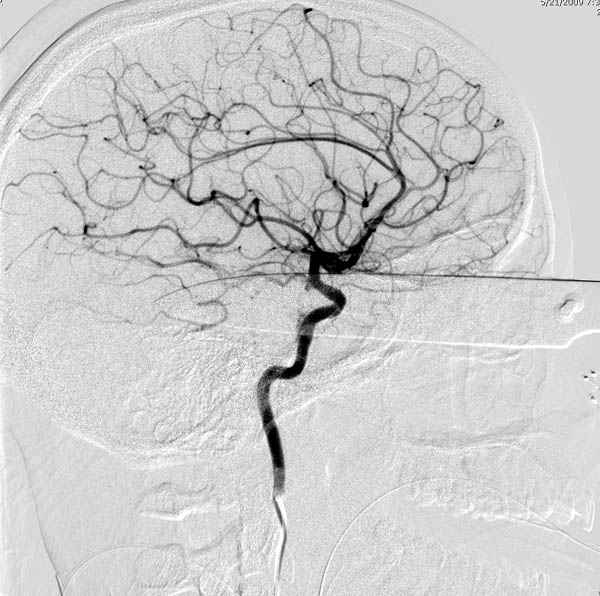

В своих выступлениях я рассказывал, что наши центры в мирное время по пенетрирующим травмам не уступает Ираку или Афганстану, и вот недавно к нам поступила больная 22 лет, травма "ножом в глаз" от бывшей подруги нынешнего "бой френда".

При поступлении в сознании, жаловалась на неприятные ощущения в глазнице.

По протоколу сделаны все необходимые исследования: рентген, ангиограмма с 3Д реконструкцией, где обнаружили что все жизненно важные сосуды не задеты, даже некоторые "сидят" изгибаясь на ноже.

Одним махом нож удалить не удалось, пришлось раскачать и потом двумя руками удалили нож. Рана без кровотечения, обработана и зашита.